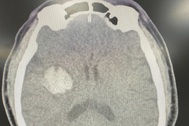

Bệnh nhân có cục máu đông gây tắc nghẽn mạch máu, dẫn đến đột quỵ (Ảnh: BV).

Vì còn trong "giờ vàng", người đàn ông được bác sĩ chỉ định sử dụng thuốc tiêu sợi huyết (rTPA) giúp tan cục máu đông (nguyên nhân gây tắc nghẽn mạch máu dẫn đến đột quỵ).